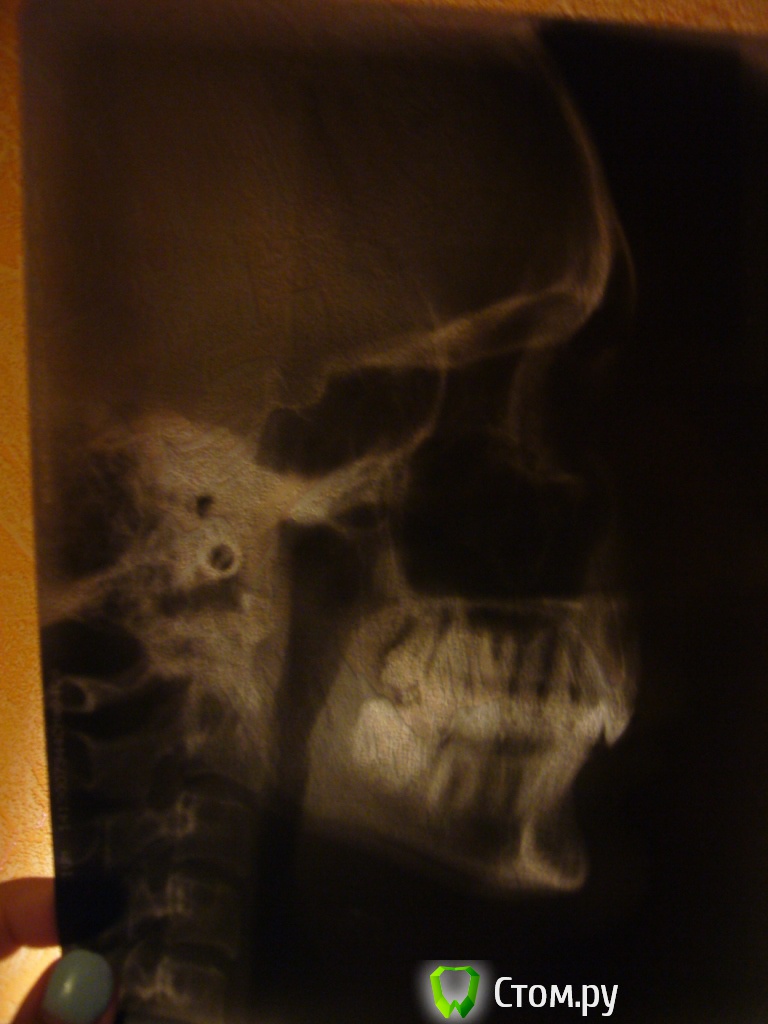

Кнопочка Опубликовано 29 июля, 2014 Автор Поделиться Опубликовано 29 июля, 2014 (изменено) Вот фото до брекетовВот зубы до брекетов,с удаленными четверкамиСлепок, правда зубы немного отколоны сбокуСнимки:и сейчас Изменено 29 июля, 2014 пользователем Кнопочка Ссылка на комментарий

Кнопочка Опубликовано 30 июля, 2014 Автор Поделиться Опубликовано 30 июля, 2014 (изменено) Ещё раз снимки поближе ОПГ и ТРГ, жду ответа 8 ки нижние мне тоже удалили,так как одна мешала,не могла вылезти, а из за второй 8 ки, у меня зуб однёрка на нижней челюсти выпер в процессе лечения.. Вскрывали десну, высверливали зуб по частям,еле как.http://ib3.keep4u.ru/b/2014/07/30/73/73e9945b514deae5710b1d7cc6d46494.jpghttp://ib3.keep4u.ru/b/2014/07/30/34/3419ca488c9374af38b2569e461427b2.jpghttp://ib3.keep4u.ru/b/2014/07/30/c2/c222f96d6150913b3beee29932b3d32b.jpghttp://ib3.keep4u.ru/b/2014/07/30/92/92cd5aa4c4af32bdab7492c20fda77c5.jpghttp://ib3.keep4u.ru/b/2014/07/30/c9/c96458724a431a4804cb1f05bf8f24c2.jpg Изменено 30 июля, 2014 пользователем Кнопочка Ссылка на комментарий